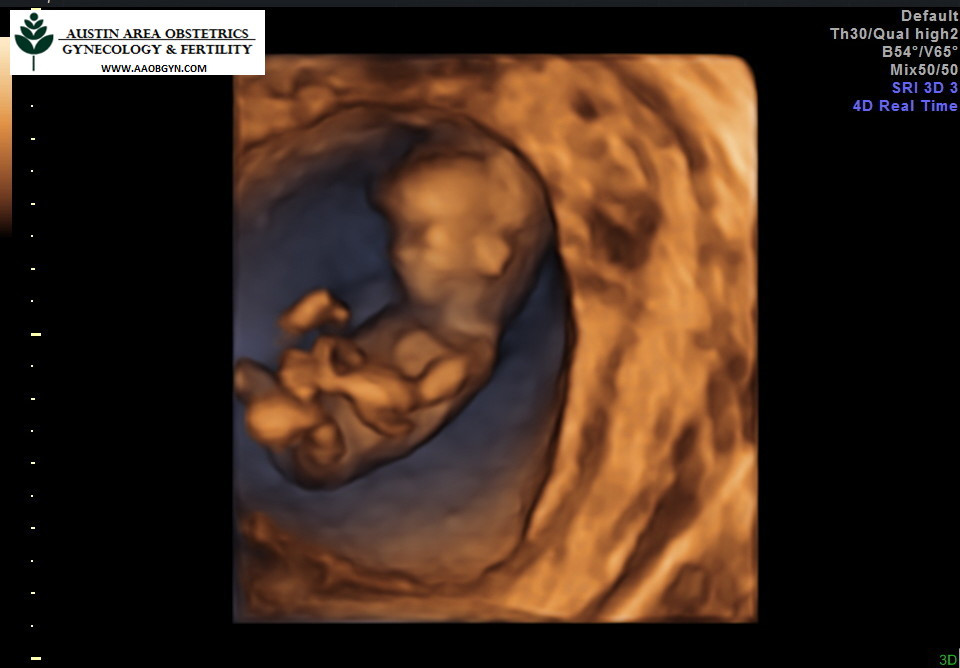

12주차

꼬물거리는 뱃속의 오스틴을 확인하고 왔다. 뱃속에서 딸꾹질도 하고 손발도 움직이는걸 보면 어찌나 귀여운지! 벌써 기관이 거의 다 생겨 엄지공주같이 사람 모습하고 있는게 너무 신기했다. 소화불량은 계속되고 살이 1키로 넘게 쪘다. 미국에서는 이 시기에 염색체검사나 유전자검사를 추가로 더하면 성별을 알 수 있다고 하는데 하지 않았다. 20주까지 기다리면 자연적으로 알게 될텐데 뭐. 건강한 태아가 더 중요하다. 1차 기형아검사를 무사히 통과했다.